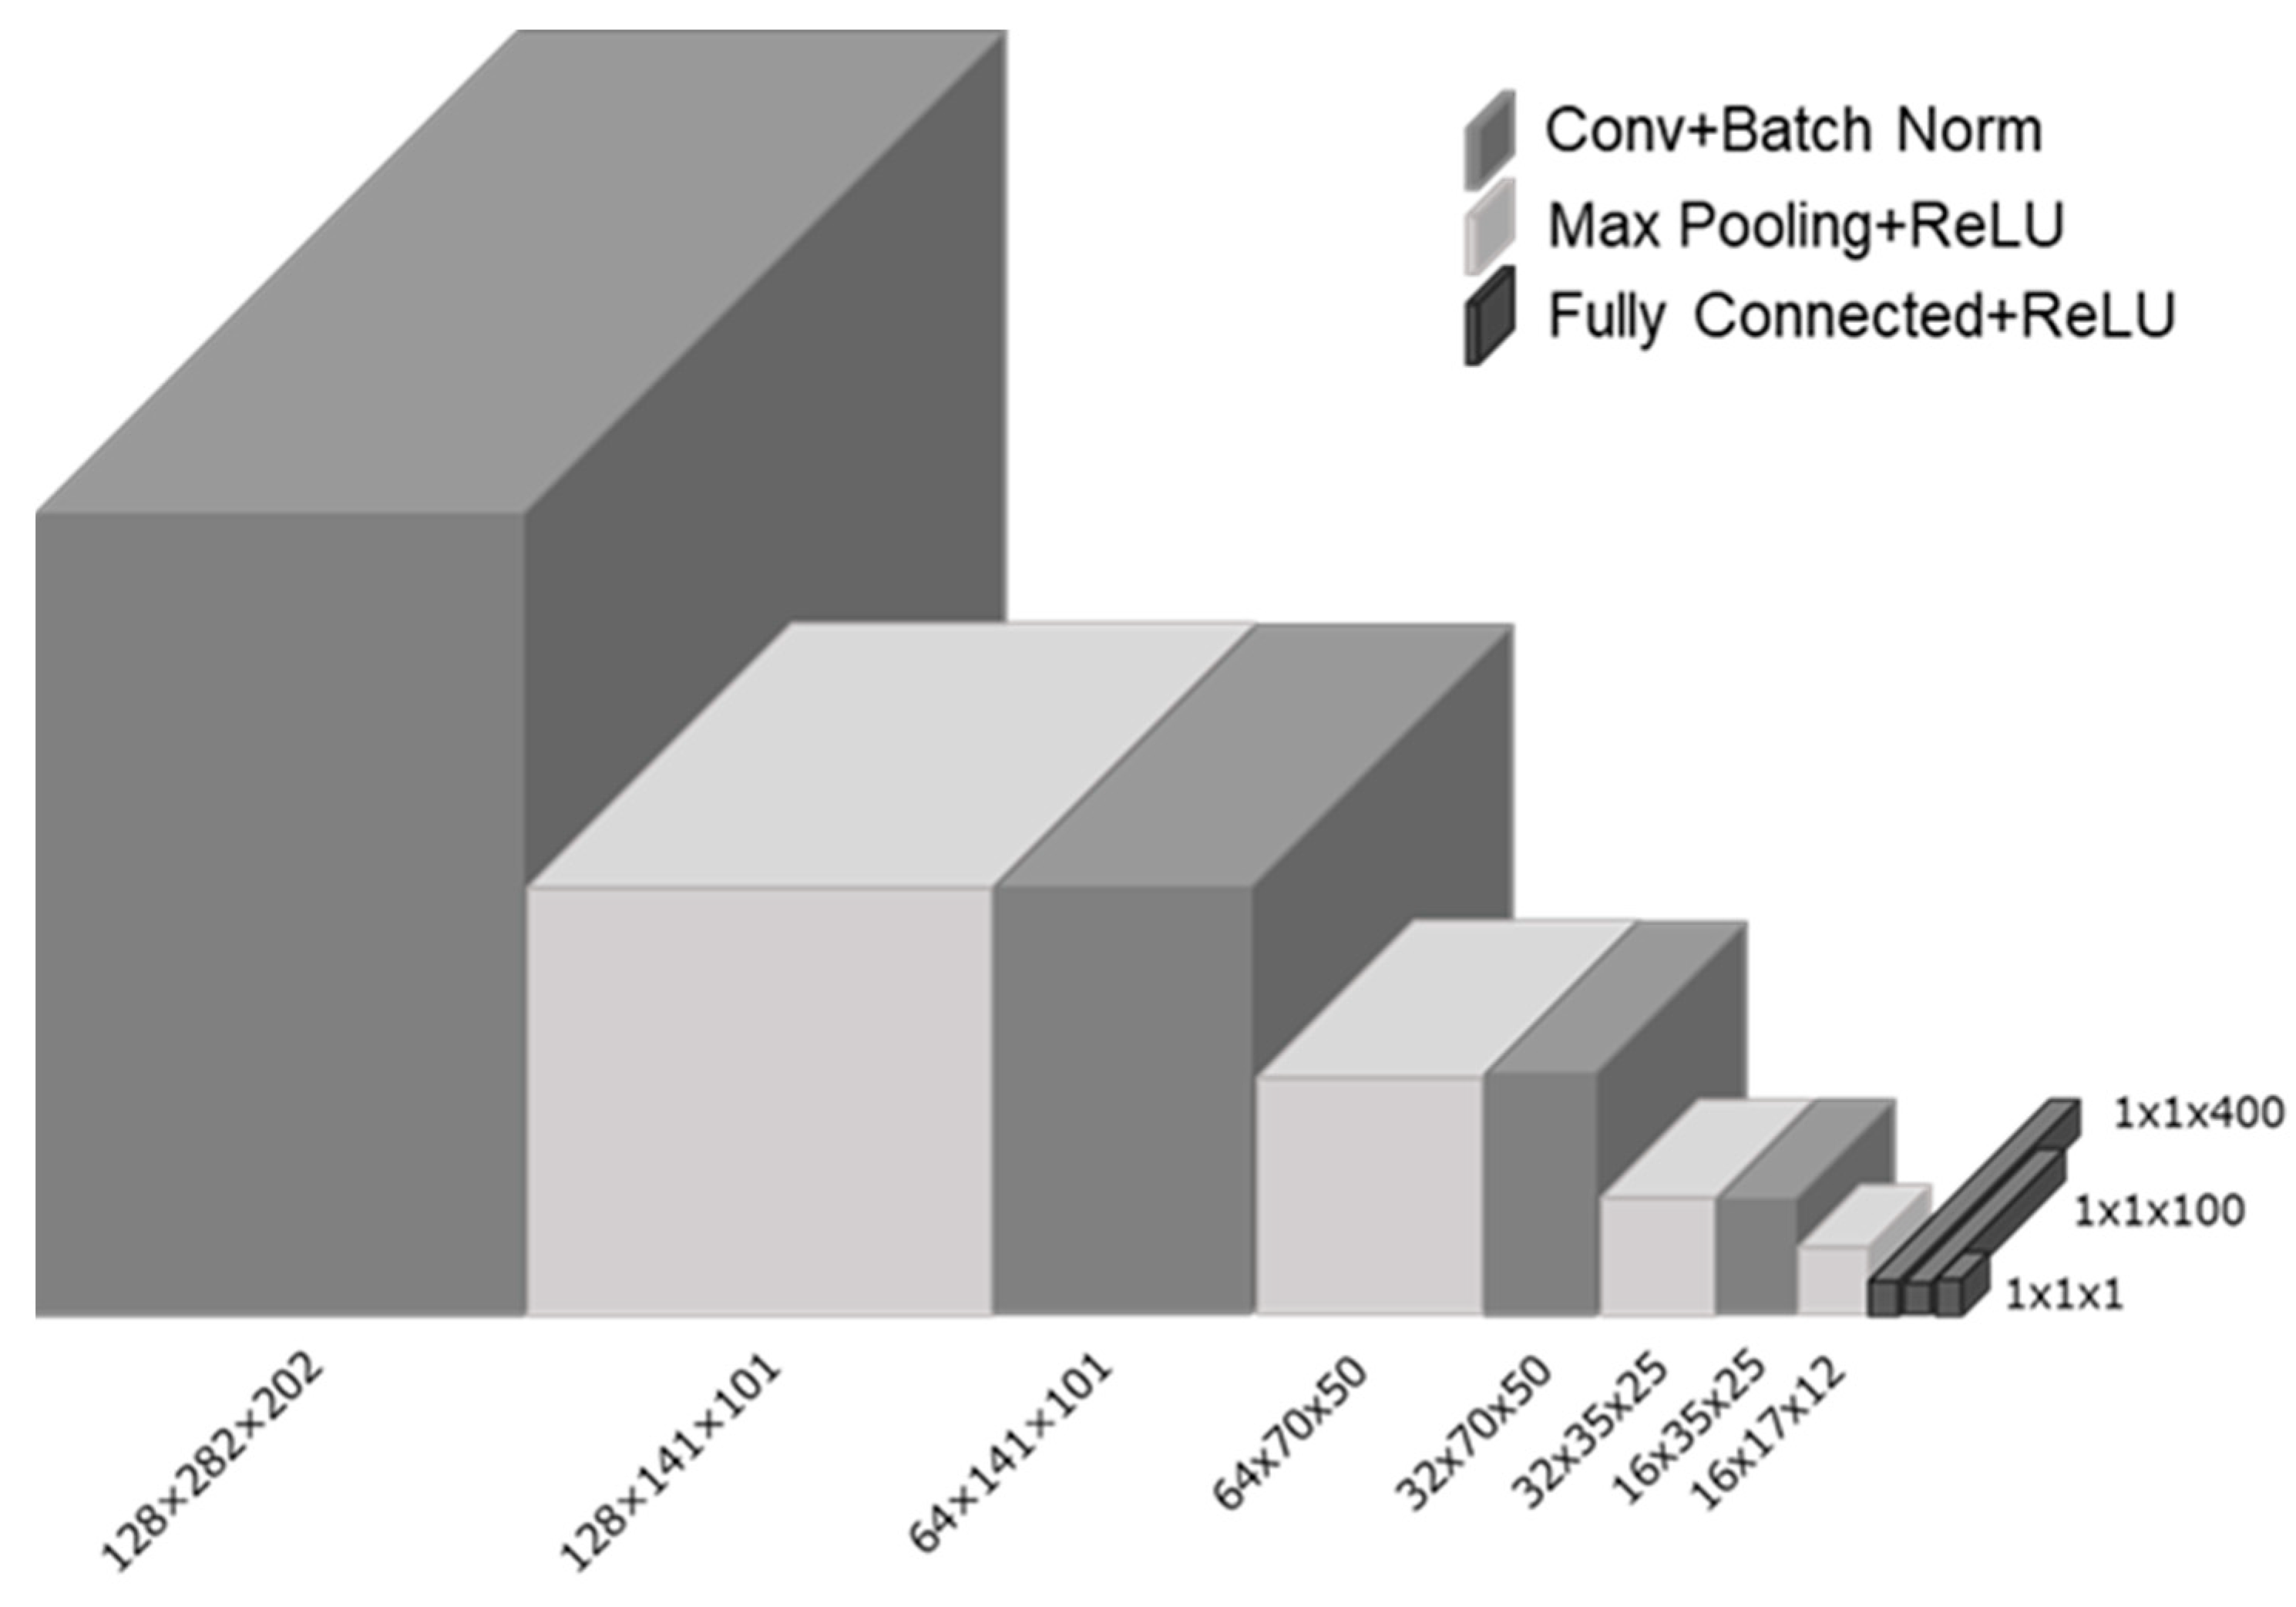

2. Materials and Methods